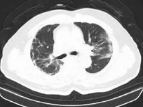

正常肺

ARDS患者肺